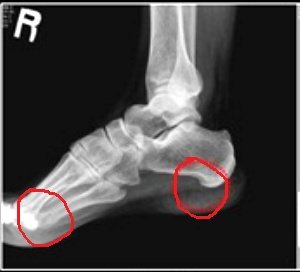

3. 두군데의 킬힐의 통증이 찾아오기 시작함;;

걸어 다닐때 아픔에 고통 참을수 없음;;